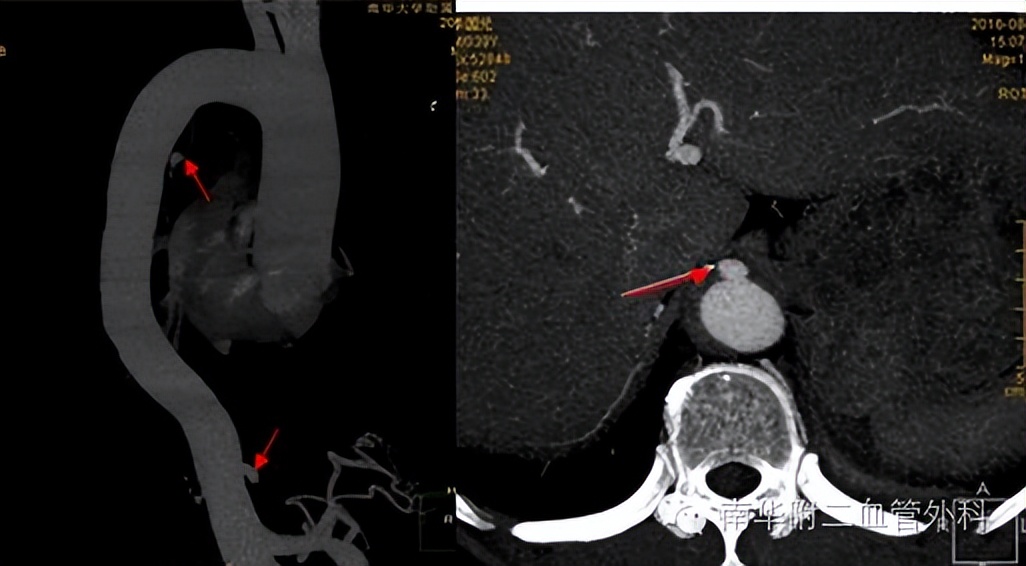

主动脉穿透性溃疡伴壁内血肿病例报告

西北专栏甘肃省人民医院陈泉教授团队分享了1例主动脉穿透性溃疡并壁